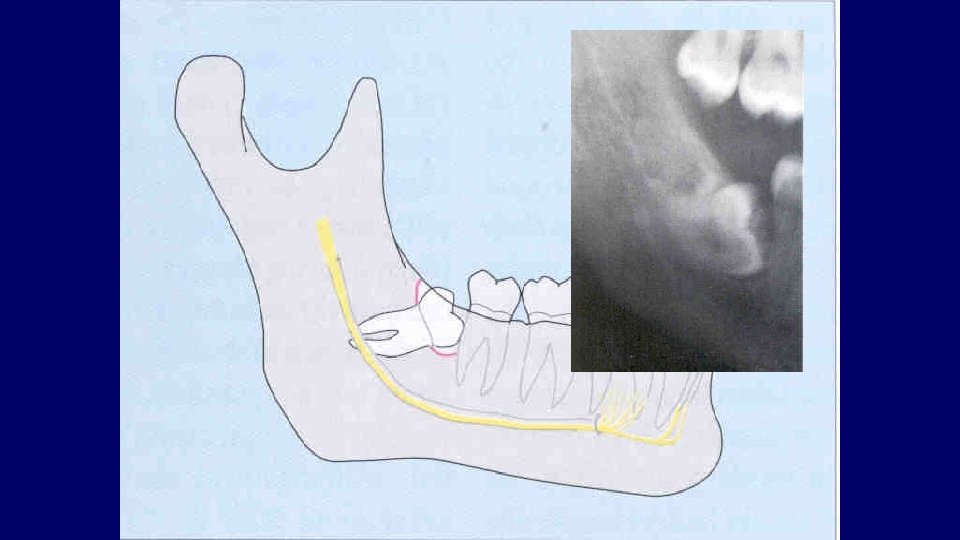

Types of impaction • Vertical • Mesioangular • Distoangular • Horizontal • Transverse

(2) Depth of impaction

Pell & Gregory Classification • Based on the amount of tooth covered by the anterior border of the ramus • The depth of the impaction relative to the adjacent tooth

Pell & Gregory • Relation to the Ramus Class III

Pell & Gregory • Depth of Impaction – Mandibular Class A Class B Class C

Pell & Gregory